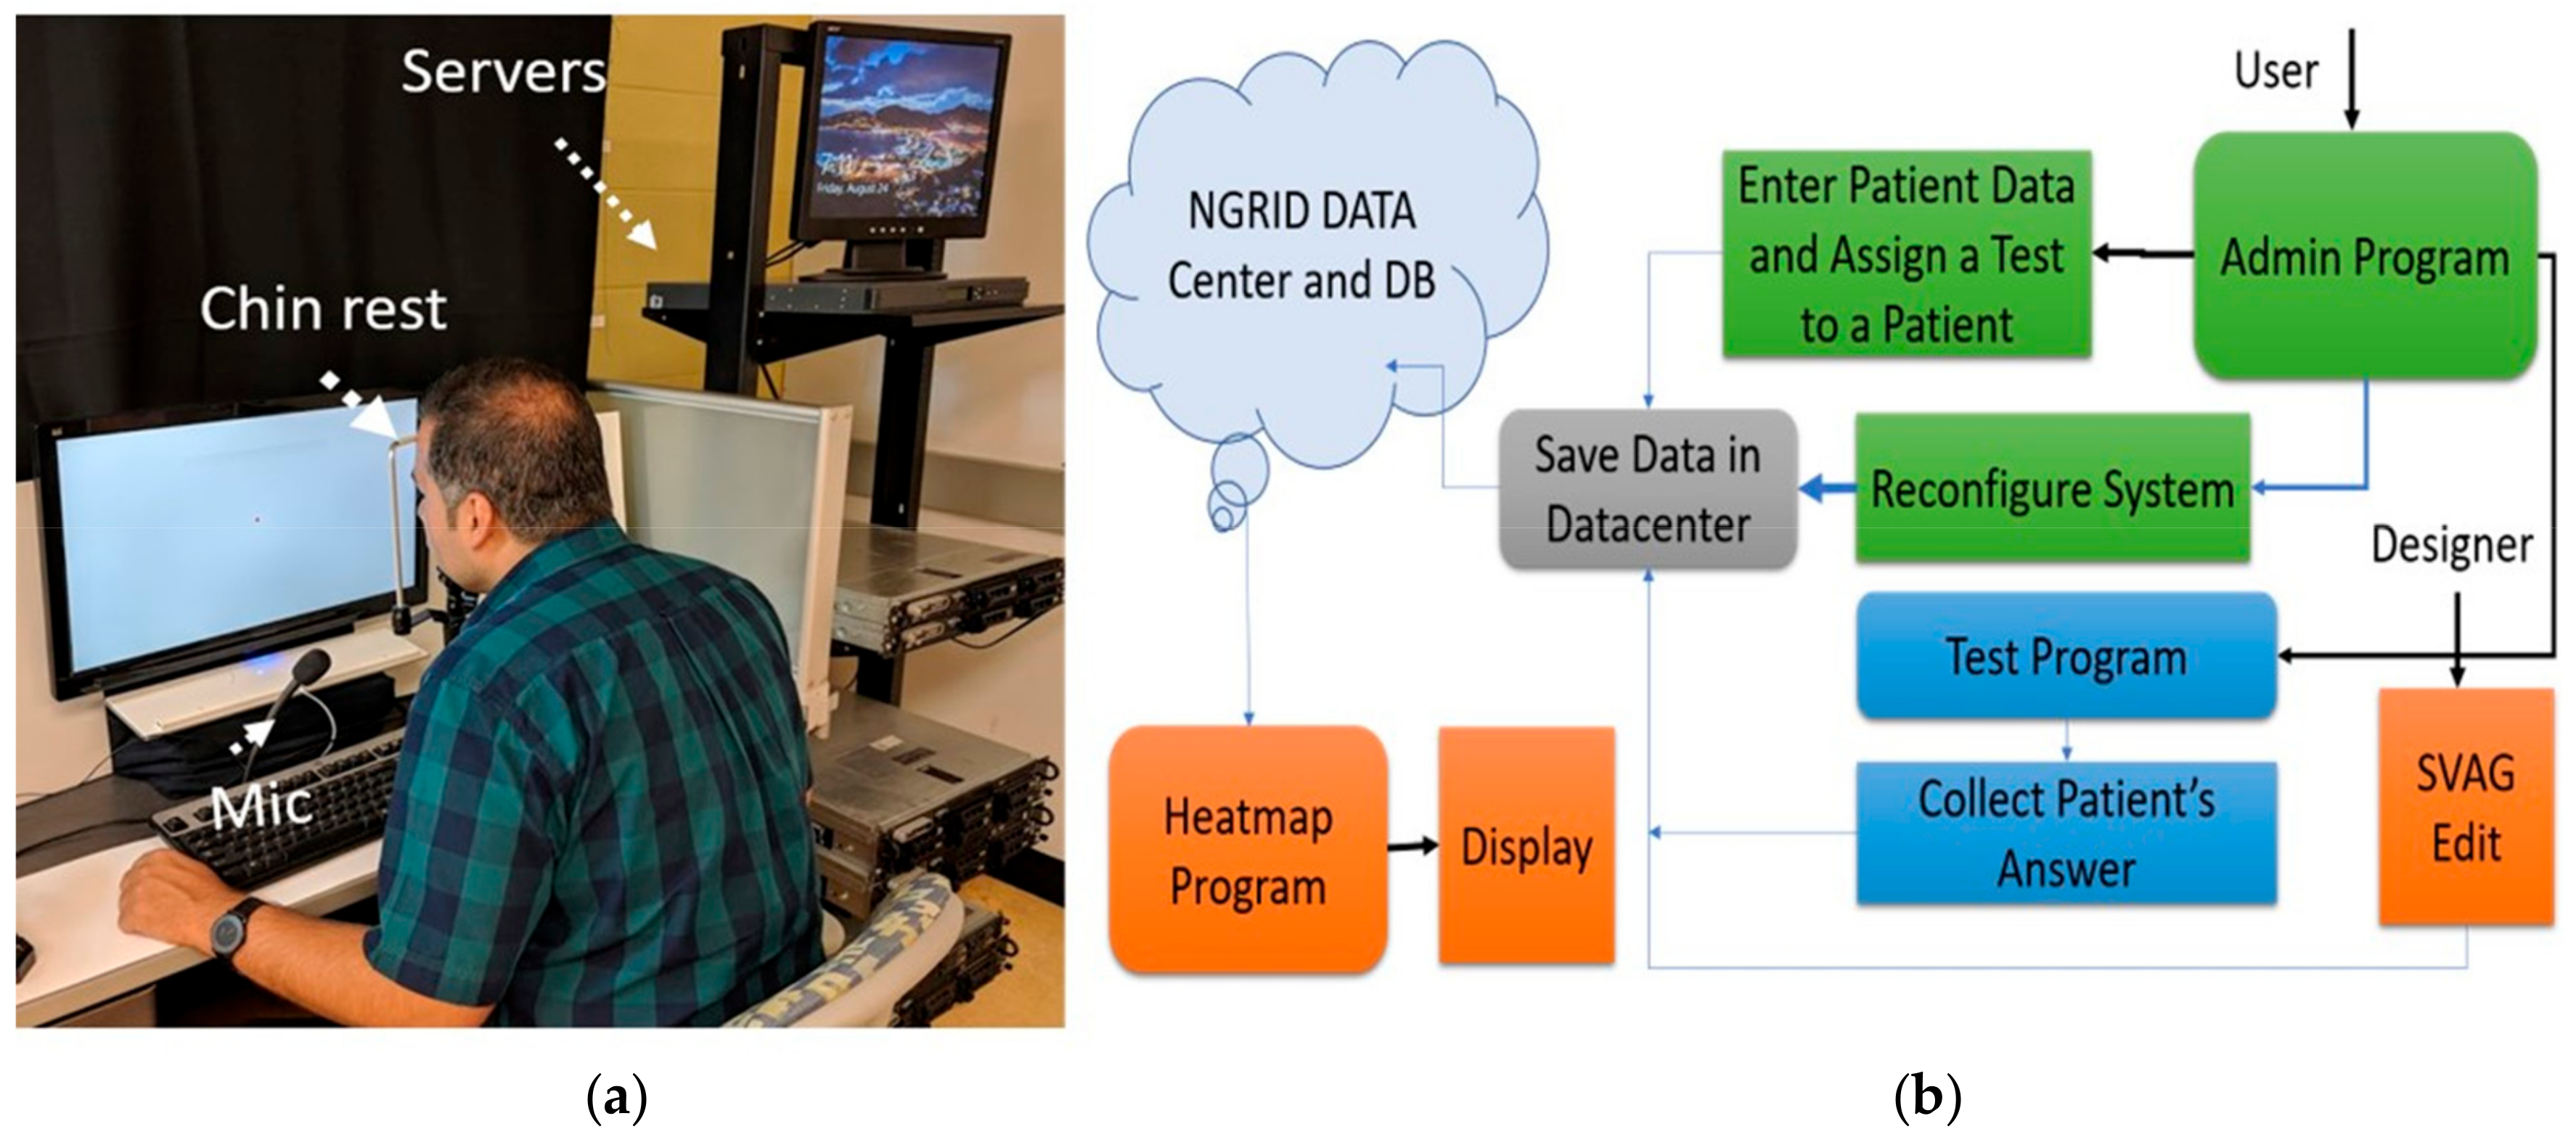

4.1. Hardware Development

4.2. Software Development

4.2.1. NGRID VD Test and SVG VD Test Editor

4.2.2. Admin Interface

4.3. Heatmap Generator

4.4. Other Programs